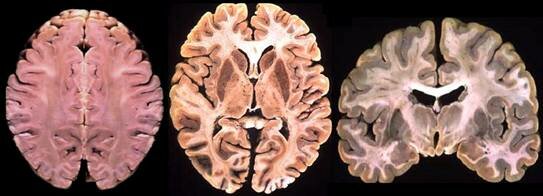

Disección del cerebro

Se disecciono el cerebro, logrando que describieran sus partes con lujo de detalle.